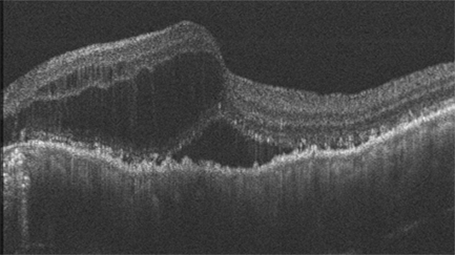

当社では、眼科で使われている検査機器「OCT(光干渉断層計)」と、最新のICT技術を組み合わせ、自宅で目の健康状態を確認できる「Home selfie OCT」を開発しました。

OCTは、目の奥の状態を細かく画像で捉えることができる機器で、当社の代表も開発に関わってきました。眼科の現場では、加齢黄斑変性や緑内障など、視力に大きく影響する病気の診断や治療に欠かせない機器です。